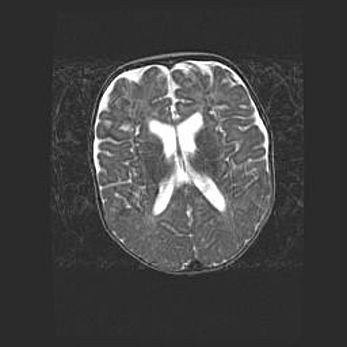

Лейкомаляция с кистозно-глиозной дегенерацией головного мозга.

Возраст: 2 месяца 25 дней

Вес: 6400 г

Окружность головы: 40 см

Срок гестации: 41 неделя

Лейкомаляцию относят к ишемически-гипоксическим повреждениям головного мозга, диагностируемым у новорожденных. При лейкомаляции в головном мозге обнаруживают очаги некроза, возникшие после тяжелой гипоксии и нарушения кровотока. В процессе морфогенеза очаги проходят три стадии: 1) развития некроза, 2) резорбции и 3) формирования глиозного рубца или кисты. Перивентрикулярная лейкомаляция (ПЛ) встречается примерно в 12% случаев среди новорожденных, обычно – у недоношенных детей, причем, частота ее зависит от массы, с которой младенец появился на свет. Наибольшее число малышей страдает лейкомаляцией, если масса при рождении 1500-2500 г.